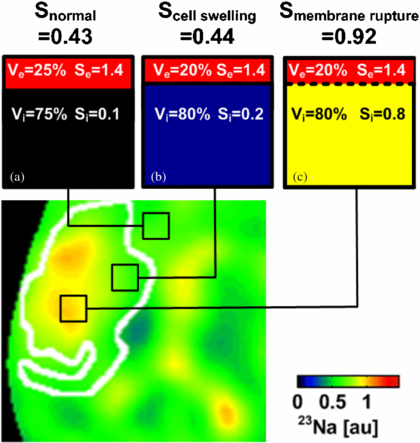

In order to understand the possible lack of sodium signal changes during the acute stroke phase, we herein extended the existing model by also allowing variations in Ve and Vi—a common pathophysiological effect due to cytotoxic edema after ischemia (McCabe et al 2009b). A graphical explanation for how sodium signal change can then be related to different stroke tissue states is given in figure 6. Extra- to intracellular 23Na signal ratios (1.4/0.1) have been chosen to closely match actual sodium concentration ratios (140 mM/10 mM) in brain tissue. Normal Stissue results from high Se = 1.4 in the extracellular compartment and low S = 0.1 in the intracellular volume compartment. Assuming Vi in normal tissue to cover approximately 75% of the given voxel, Stissue is expected to be 0.43 (figure 6(a)).

Figure 6. 23Na image (zoomed in to the stroke region on the left hemisphere) taken from figure 5 at 9 h after stroke with a superimposed region of restricted hydrogen diffusion (white line). (a) 23Na signal in brain tissue originates from intra- and extracellular volumes within a given voxel. (b) Voxel located within ADC lesion showing the normal 23Na signal. Please note that a marginal volumetric cell expansion from 75% to 80% compensates for a 100% increase in intracellular 23Na concentration with no effect on the overall 23Na signal. Hence, in this case, the 23Na signal did not increase in cellular edema tissue while the tissue viability could have been restored via arterial reperfusion. (c) A drastic change in the 23Na signal occurs after cell membrane rupture indicating tissue viability loss.

Standard imageInitially, as soon as the cellular membrane function is disrupted, 23Na ions are accumulated inside cells and consequently the intracellular 23Na signal increases. The disturbed 23Na concentration ratio between intra- and extracellular spaces is compensated for by a strong influx of water into the cells and a subsequent swell-up of cells (cytotoxic edema). The intracellular space increases (McCabe et al 2009b), which results in decreased water mobility and a subsequent drop in the 1H ADC. It is worth noting that subsequently a change in an intracellular volume fraction by only 7% from 75% to 80% compensates for an intracellular sodium signal increase of 100% from 0.1 to 0.2 (figure 6(b)). Hence, the 23Na concentration and 23Na concentration weighted signal as measured by 23Na-MRI may remain constant or decrease slightly in still-viable stroke tissue rather than exhibit an increase.

In the case of cell membrane rupture, the membrane barrier between the intra- and extracellular compartments is removed and 23Na ions are allowed to freely diffuse into the considered voxel with assumed ion supply from the neighboring extracellular space and the perfused vascular compartments carrying a high 23Na content (figure 6(c)), of which the 23Na concentration is regulated globally by the kidney function. Up to three-fold increase in TSC has been measured in permanently damaged stroke tissue in mouse (Heiler et al 2011), rat (Wetterling et al 2012a, Jones et al 2006, Wetterling et al 2010, Yushmanov et al 2009) and man (Thulborn et al 2005, Tsang et al 2011, Shimizu et al 1993) before. However, the transition processes between those two states must be considered carefully in order to understand all possible 23Na MR signal changes or the lack thereof in hypoperfused, but still viable penumbra tissue.